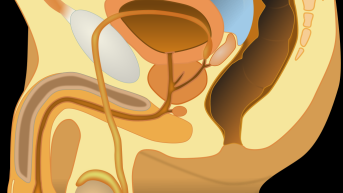

Infertilidade conjugal é o nome dado pela OMS (Organização Mundial da Saúde) para a ausência de gestação...

O corpo humano é constituído por diversas partes que gostamos de comparar a engrenagens de...